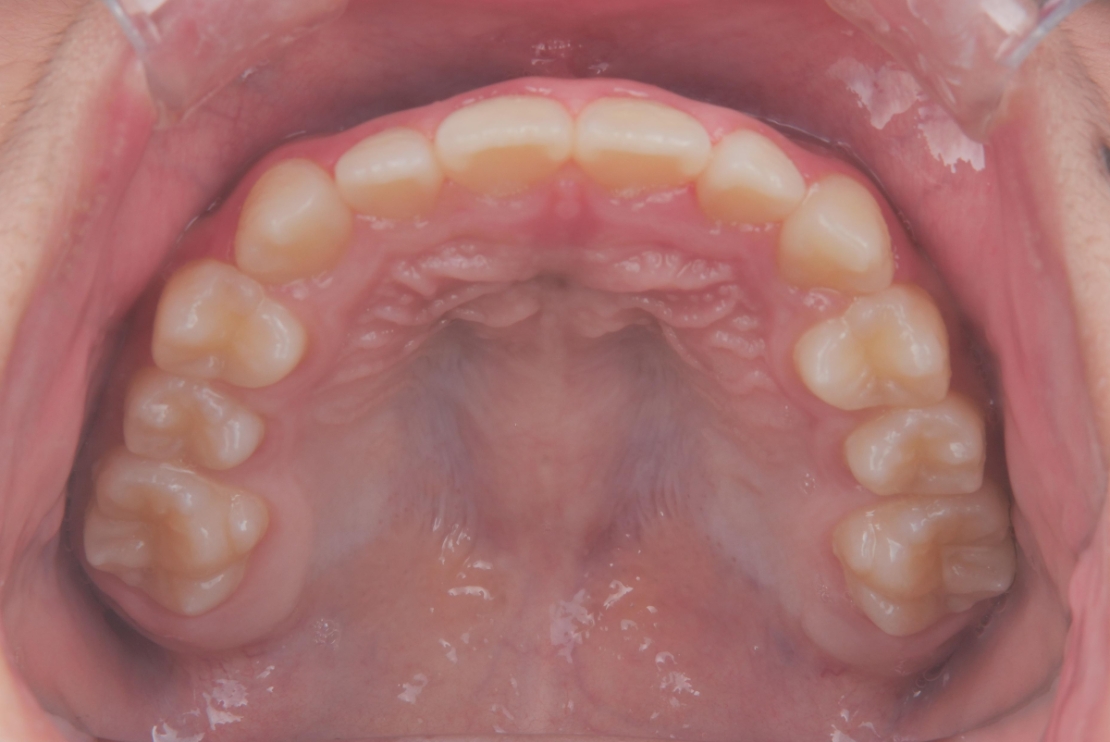

BEFORE

| 年齢・性別 | 9歳男児 |

|---|---|

| 主訴 | すきっ歯とガタガタが気になる |

| 施術内容 | プレオルソ+インビザラインファースト |

| 治療期間 | 1年半 |

| 費用 | 594,000円(税込) |